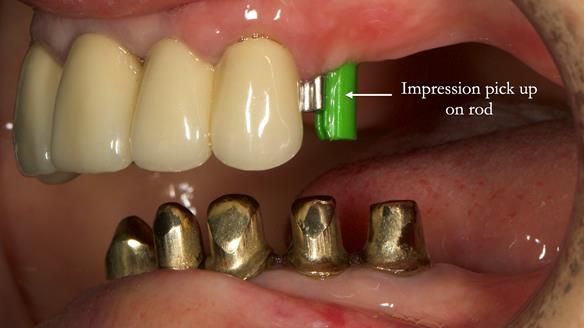

Replacement lower overdenture & upper RPD for Jackie

This Newsletter show Jackie’s case from start to finish – a technically demanding case involving replacing a telescopic crown-supported lower overdenture and an upper precision attachment-retained partial denture.